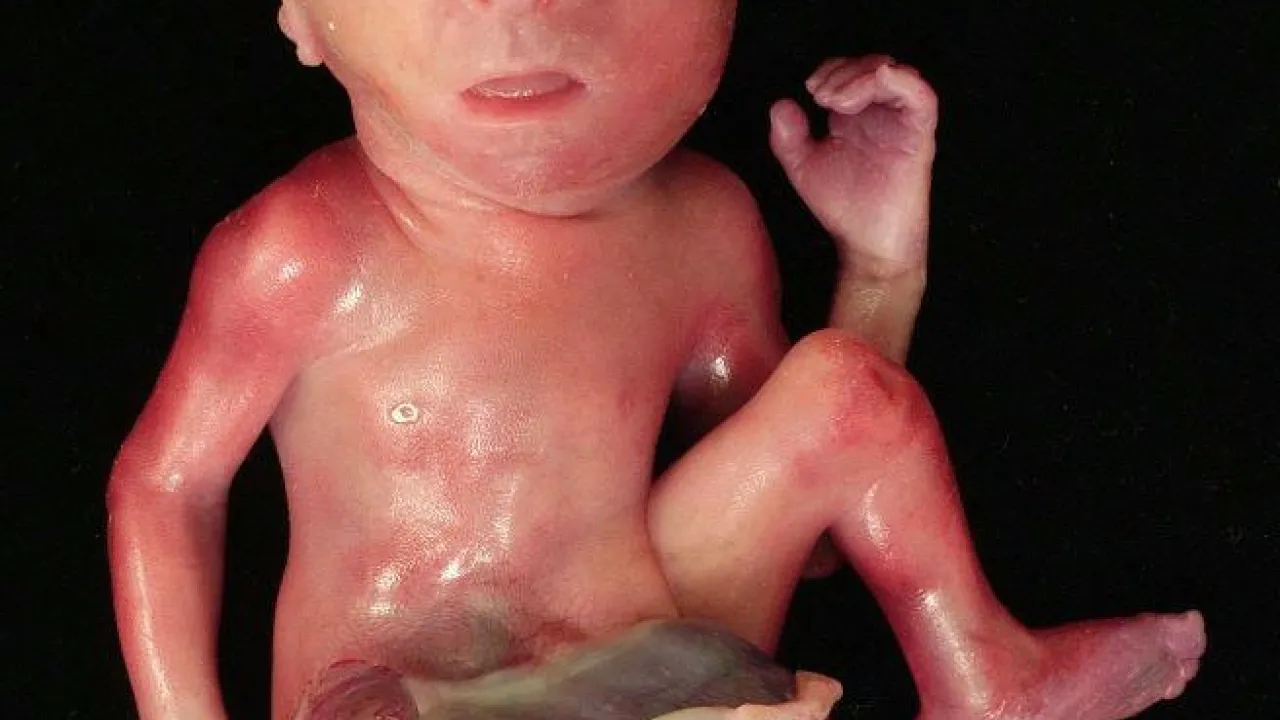

Body Morphology, OEIS Complex